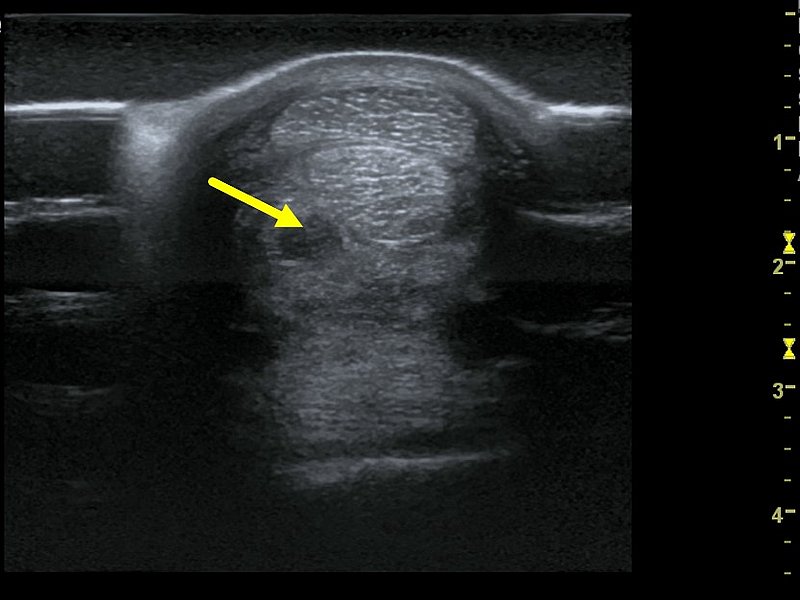

Ultraschall

Die ultrasonographische Untersuchung findet in der Pferdemedizin ein vielfältiges Einsatzgebiet, da sie für die Darstellung von Weichteilstrukturen wie z.B. Sehnen, Bändern, Darm und Organen wie Herz und Nieren besonders geeignet ist. Die Klinik für Pferde verfügt über mehrere hochmoderne Ultraschallgeräte, die für spezielle Fragestellungen (z.B. Herzultraschall oder Sehnenerkrankung) zur Verfügung stehen.

Deshalb wird die Ultraschalluntersuchung sowohl in der Inneren Medizin als auch in der Orthopädie täglich als bildgebendes Verfahren eingesetzt. Im Gegensatz zum Röntgen arbeitet die Ultraschalluntersuchung mit Schallwellen und nicht mit Röntgenstrahlung, so dass ihr Pferd keiner Strahlenbelastung ausgesetzt ist. Meist ist auch keine Sedation notwendig, jedoch muss häufig eine Schur des Haarkleides an den zu untersuchenden Bereichen vorgenommen werden, um eine bessere Bildqualität zu erhalten.